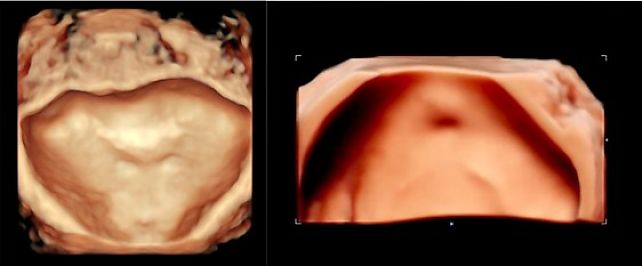

Transabdominal three-dimensional ultrasound image (3D) of the urinary bladder triangle demonstrating normal anatomy.

10

Bladder endometriotic nodule visualized on three-dimensional ultrasound.